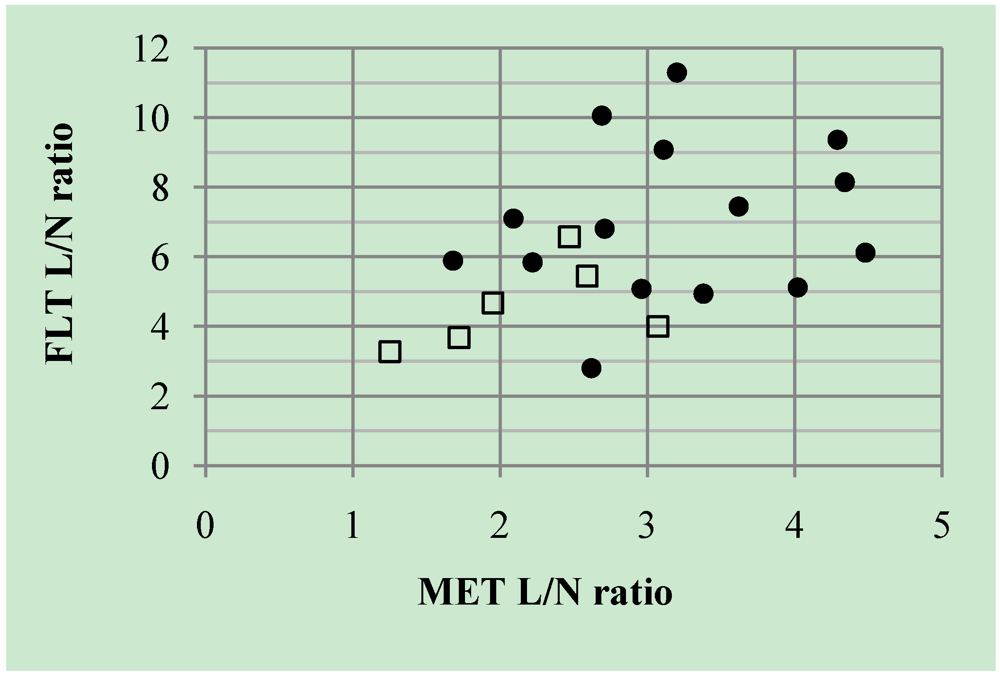

2.1.2. Semi-Quantitative Analysis